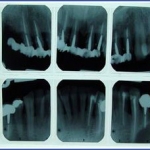

3.צילום סטטוס:

זהו צילום שנעשה במכון רנטגן וכולל 14-18 צילומים פריאפיקלים המכילים את כל השיניים בפה.

צילום סטטוס נעשה בדרך כלל כאמצעי אבחנתי לאנשים שעוברים\עברו טיפול שיקומי בפה, אנשים שיש להם בעיית נסיגת עצם והחניכיים –הצילום מאפשר לראות את גובה העצם המאחזת את השיניים.

במקרים רבים רופא השיניים יבקש מכם להביא צילום סטטוס הכולל גם צילומי נשך בערכה אחת.

4. צילום סטטוס מקביליות:

במקרים רבים רופא השיניים יפנה אותך לבצע צילום "סטטוס מקביליות" . ובכן זהו בעצם הדבר האמיתי ולא צילום הסטטוס הרגיל..

הצילום בנוי מ 20 צילומים פריאפיקלים (בודדים), כאשר לצילום זה יצורפו תמיד גם 4 צילומי נשך.

בצילום זה משתמשים בפילים צר יותר לשיניים קדמיות ובכל צילום מתמקדים בשן אחת בלבד, בניגוד לסטטוס רגיל שבפילים אחד מתמקדים בכמה שיניים במקביל.

בצילום סטטוס מקביליות, הצילום עצמו מוחזק בפה באמצעות מכשור פלסטי נקי ,אסתטי וברוב המקרים אף סטרילי. הקרן ממוקדת ואינה מתפשטת לצדדים.

הצילום קרוי בשפה מקצועית "אורתורדיאלי" והוא בעצם כמו "צל" של השן , אמנם מוגדל אך ביחס דומה.